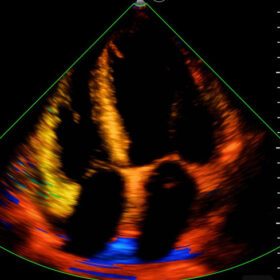

Mindray I3P WiFi Probe Image Gallery and Videos

Display mode: B, B/M, and Color, PW, PDI